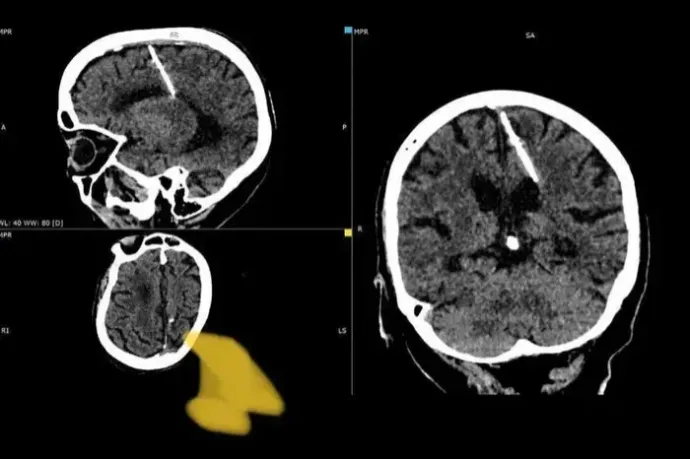

Születése óta egy három centiméteres tűvel az agyában él egy nyolcvanéves nő Oroszországban

Az orvosok szerint a szülők az éhínség alatt a tűvel próbálták megölni a magzatot, de nem sikerült.